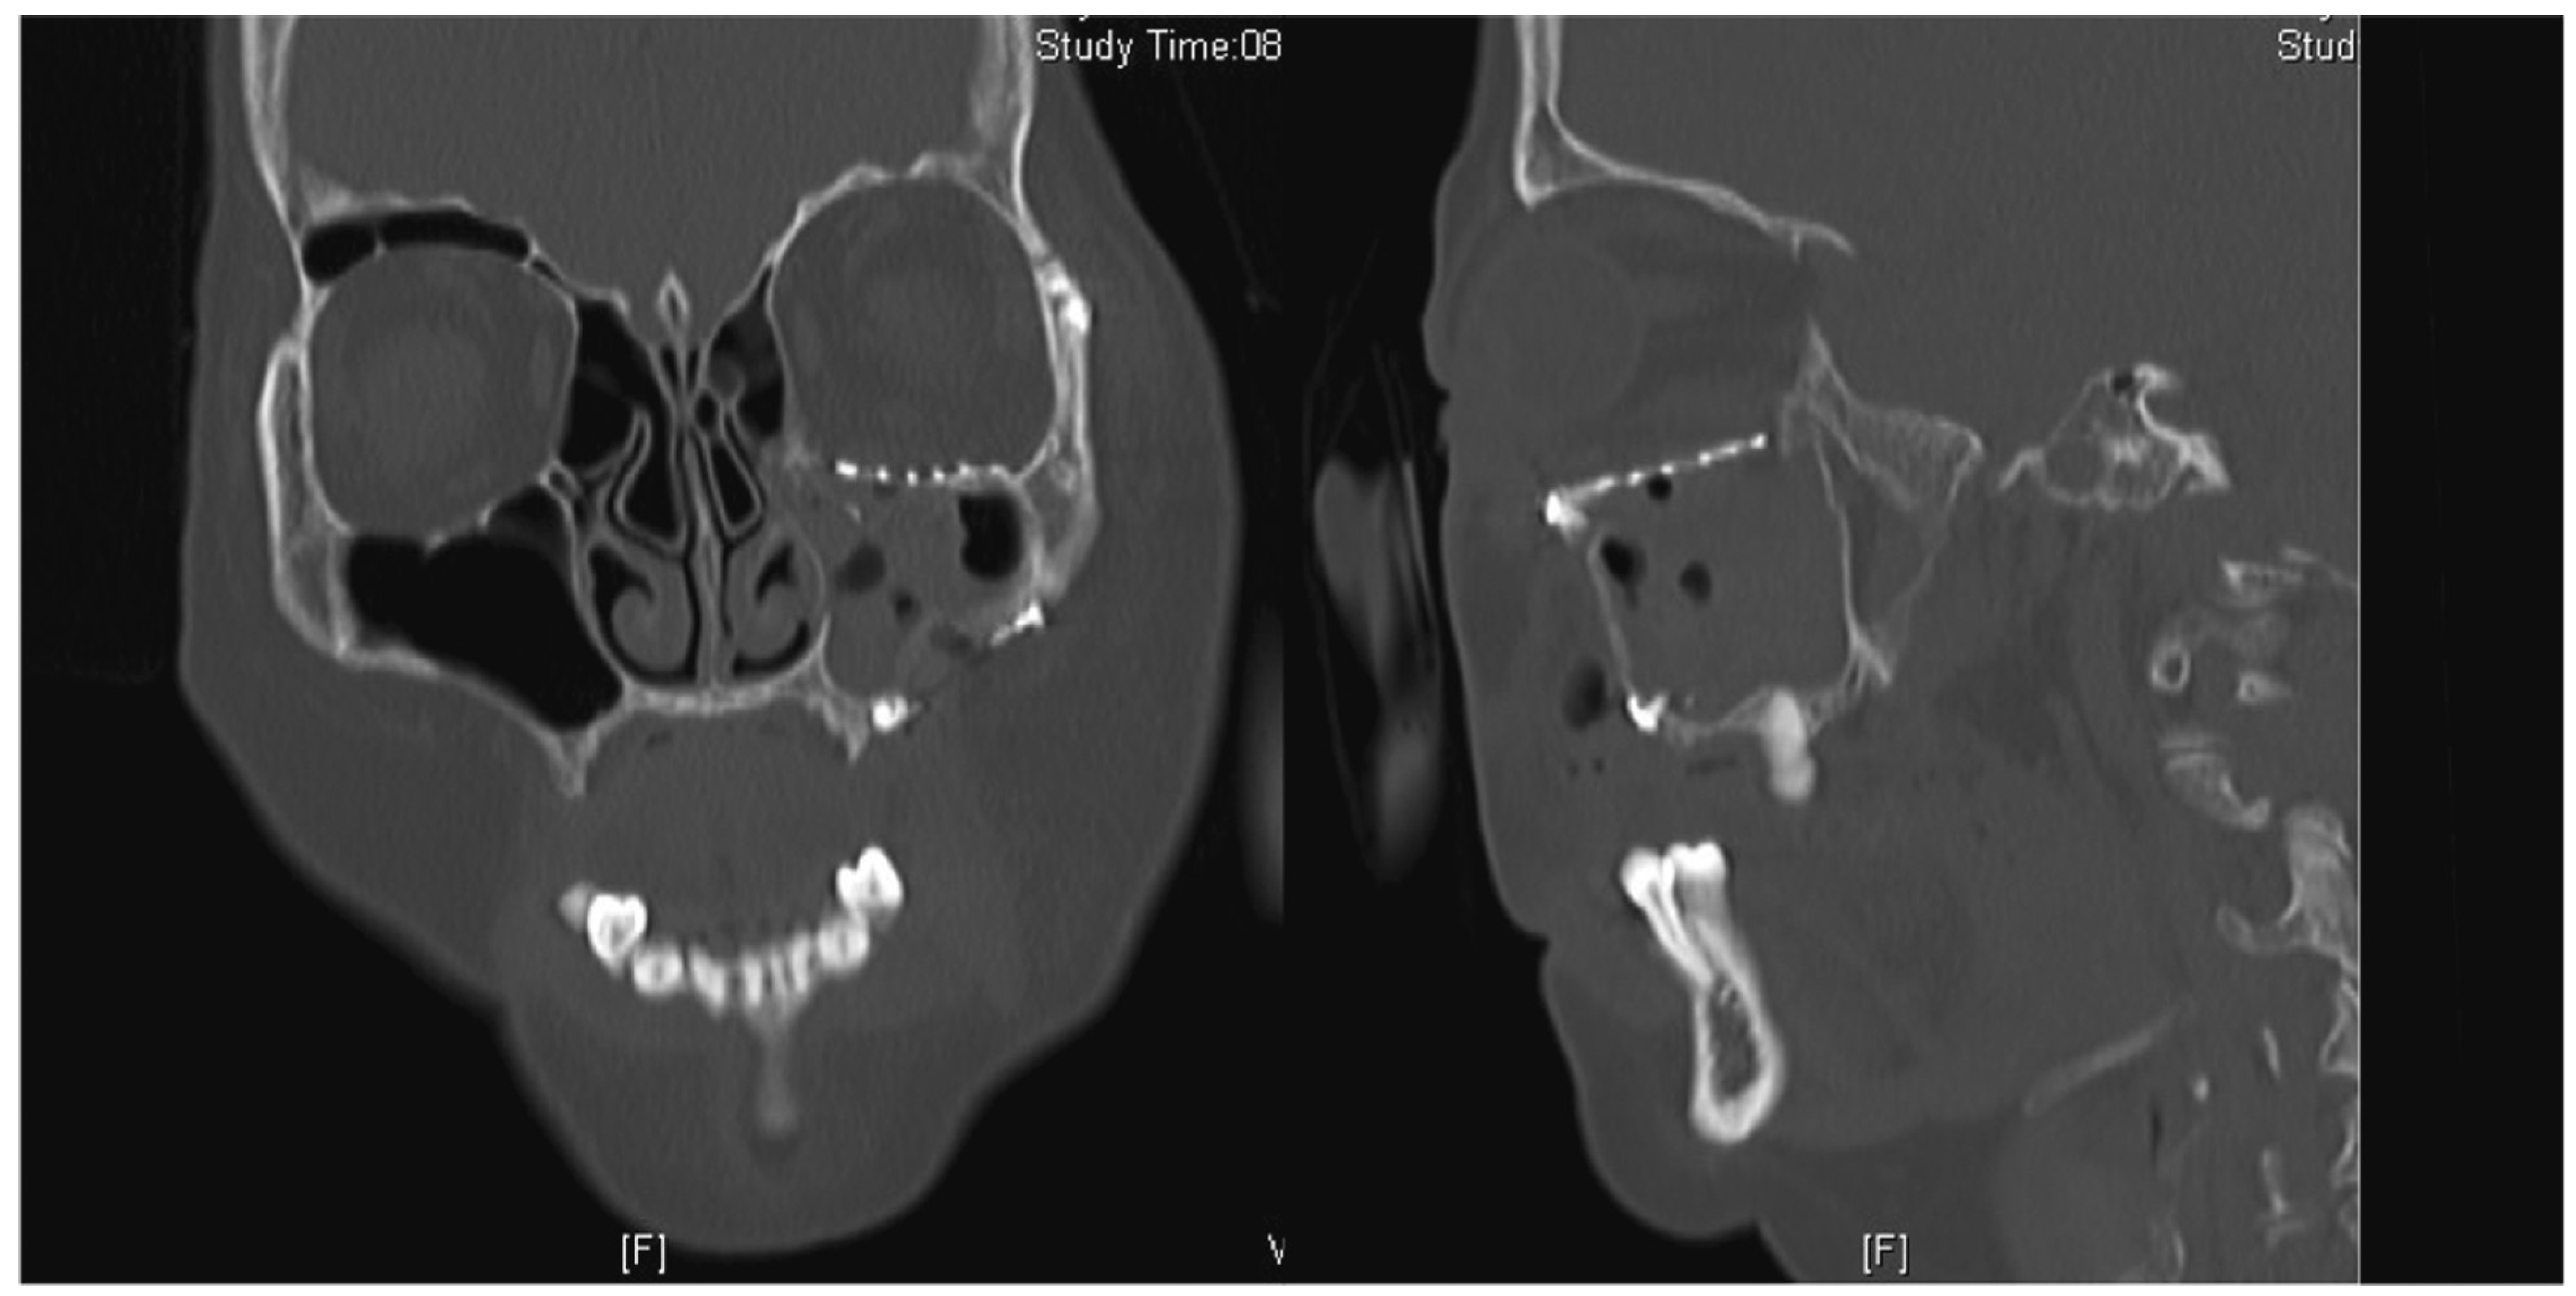

A 66-year-old woman sustained a left ZMC fracture and orbital floor fracture following a fall (Figure 5), resulting in left enophthalmos and diplopia on upward gaze. She underwent ORIF and orbital floor reconstruction 12 days after the injury. Both the 0.4-mm titanium orbital mesh and orbital rim plate were used (Figure 6). Postoperatively, she complained of progressive worsening of left upward gaze diplopia, starting around 2 weeks postoperatively and worsening over 4 weeks. There was also dimpling noted over the left lower lid due to lid retraction; however, forced-duction test was negative. She was given lower eyelid scar massage, which was performed in an upward oblique fashion from medial to lateral, and steroid injections (8 IU of triamcinolone) into the lower eyelid. On the 9th week postoperative follow-up, she reported improvement of diplopia but still had lower eyelid retraction and a tugging sensation (Figure 7). She was then given 0.3 mL of hyaluronic acid (HA) filler (Restylane; Galderma, Lausanne, Switzerland) into the posterior lamella space to correct the lower eyelid retraction. She experienced immediate and sustained (at 1 month) relief of symptoms of tugging and eyelid retraction.

Figure 6. Coronal and sagittal cuts of the postoperative CT scan of the face (Case 2) demonstrating reduction of all periorbita. Although the posterior edge of the plate is slightly depressed, there is no tethering of the inferior rectus muscle.